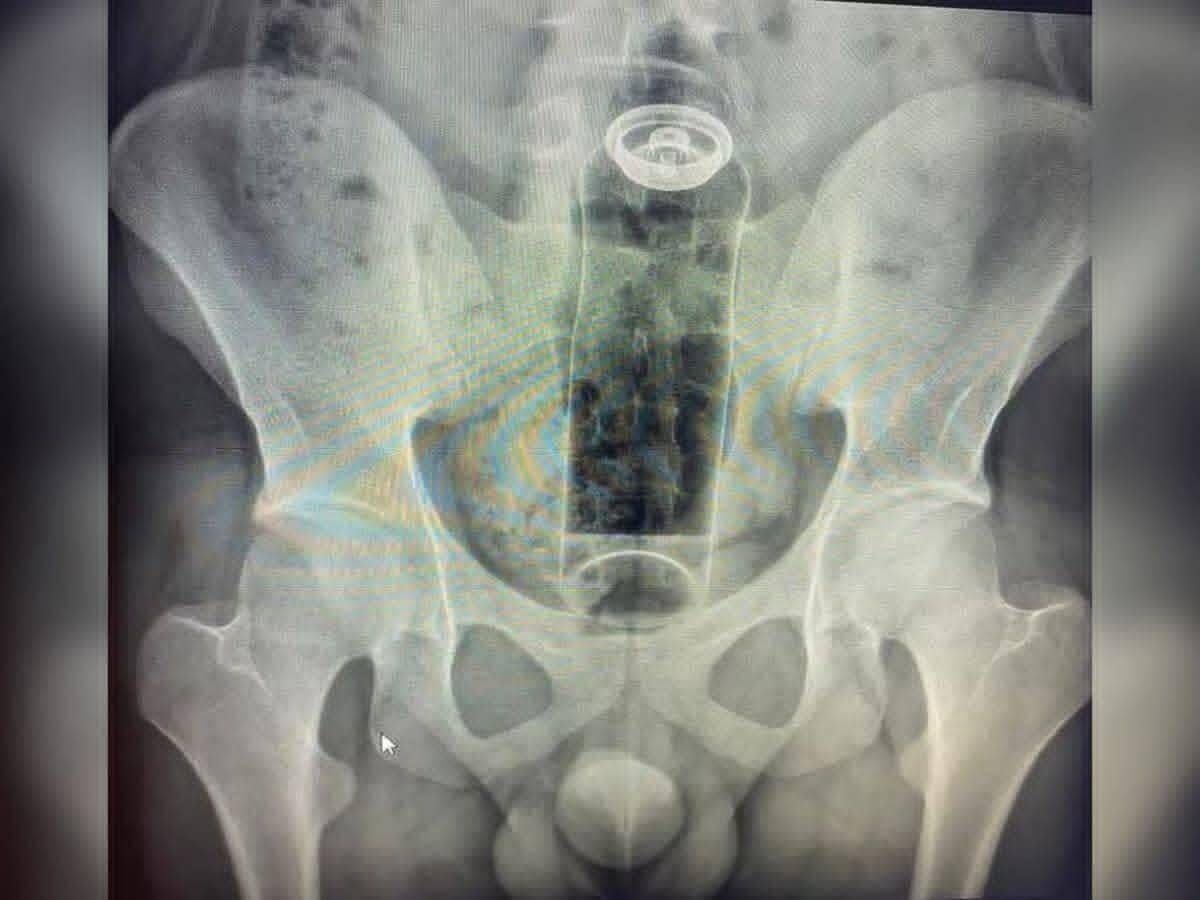

Um jovem de 19 anos precisou ser internado às pressas após a embalagem de um desodorante ficar presa no ânus durante uma prática sexual. O caso ocorreu quando o objeto acabou sendo empurrado para o interior do intestino, impossibilitando a retirada manual em casa.

Ao perceber a gravidade da situação, o paciente procurou atendimento hospitalar relatando dor e desconforto abdominal. Exames realizados pela equipe médica confirmaram a presença do objeto na região retal, sendo necessária uma intervenção especializada para a remoção segura.